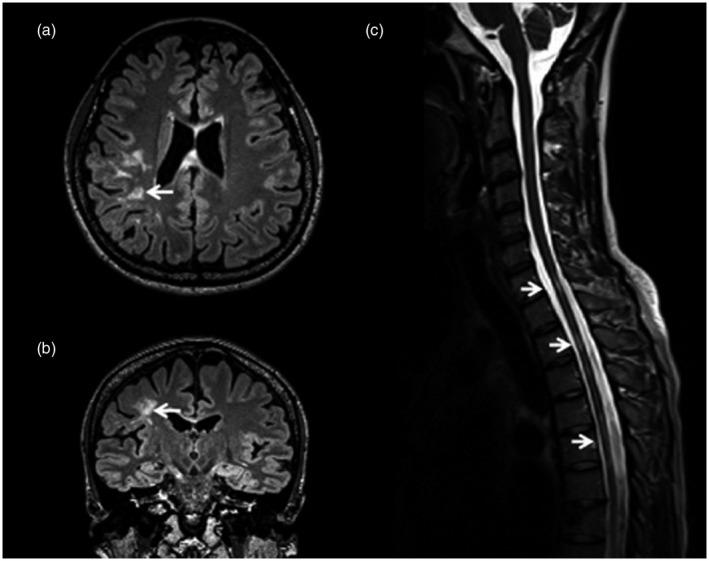

MOGAD-MRI 和 OCT 的临床和神经影像学表现。

Clinical and neuroimaging findings in MOGAD-MRI and OCT.

Myelin oligodendrocyte glycoprotein antibody-associated disorders (MOGAD) are rare in both children and adults, and have been recently suggested to be an autoimmune neuroinflammatory group of disorders that are different from aquaporin-4 autoantibody-associated neuromyelitis optica spectrum disorder and from classic multiple sclerosis. In-vivo imaging of the MOGAD patient central nervous system has shown some distinguishing features when evaluating magnetic resonance imaging of the brain, spinal cord and optic nerves, as well as retinal imaging using optical coherence tomography. In this review, we discuss key clinical and neuroimaging characteristics of paediatric and adult MOGAD. We describe how these imaging techniques may be used to study this group of disorders and discuss how image analysis methods have led to recent insights for consideration in future studies.

髓鞘少突胶质细胞糖蛋白抗体相关疾病(MOGAD)在儿童和成人中均较为罕见,最近有研究提示其为一种不同于水通道蛋白 4 自身抗体相关视神经脊髓炎谱系疾病和经典多发性硬化的自身免疫性神经炎症性疾病组。MOGAD 患者中枢神经系统的体内影像学检查在评估脑、脊髓和视神经磁共振成像以及使用光学相干断层扫描进行视网膜成像时显示出一些独特特征。在这篇综述中,我们讨论了儿科和成人 MOGAD 的关键临床和神经影像学特征。我们描述了这些影像学技术如何用于研究这组疾病,并讨论了图像分析方法如何为未来研究提供新的思路。